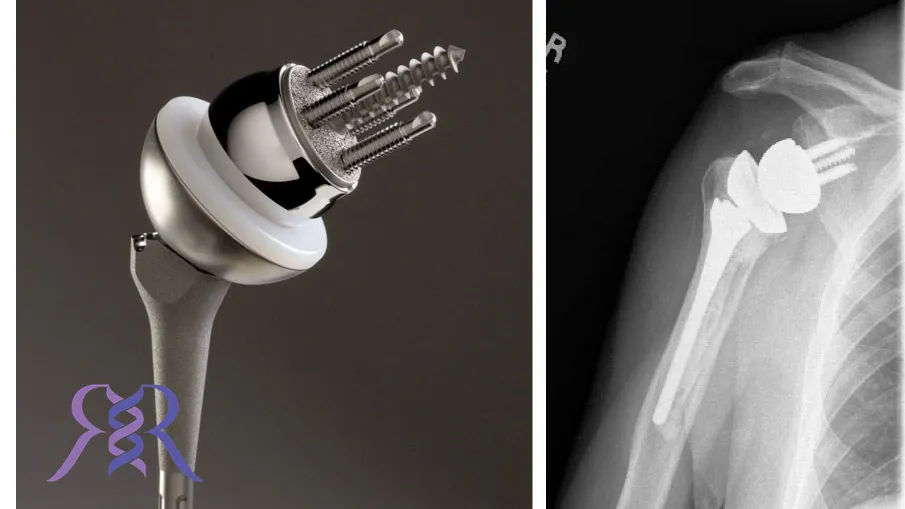

پروتز شانه به قطعات مصنوعی گفته میشود که برای جایگزینی مفصل آسیبدیده یا تخریبشده شانه استفاده میشوند. این پروتزها به منظور بازگرداندن حرکت طبیعی شانه و کاهش درد شدید طراحی شدهاند. پروتز شانه به افرادی که از مشکلات شدید مفصلی رنج میبرند کمک میکند تا کیفیت زندگی خود را بهبود بخشند و از حرکت و کارکرد طبیعی بازوها لذت ببرند.

انواع پروتز شانه بسته به نوع آسیب و نیازهای بیمار متفاوت است. این پروتزها با هدف بهبود عملکرد شانه و کاهش درد طراحی شدهاند. در ادامه به بررسی دقیقتر انواع پروتز شانه میپردازیم:

پروتز شانه کامل آناتومیک (Anatomic Total Shoulder Replacement)

این نوع از پروتز شانه برای بیمارانی مناسب است که هر دو بخش مفصل شانه، یعنی کاسه و توپی، آسیب دیدهاند. در این روش، هر دو بخش با قطعات مصنوعی جایگزین میشوند. پروتز شانه کامل آناتومیک به بیمار کمک میکند تا حرکت طبیعی شانه را بازیابد و درد ناشی از آسیب را کاهش دهد. این نوع پروتز برای بیمارانی که دچار تخریب گسترده مفصل شانه هستند بسیار مناسب است.

پروتز شانه جزئی یا همی آرتروپلاستی (Hemiarthroplasty)

در این نوع از انواع پروتز شانه، تنها بخش توپی شانه جایگزین میشود و کاسه مفصل سالم باقی میماند. پروتز شانه جزئی برای بیمارانی مناسب است که فقط بخش کوچکی از مفصل شانه آنها آسیب دیده است. این نوع جراحی میتواند زمان بهبودی کوتاهتری داشته باشد و بیمار سریعتر به فعالیتهای روزانه خود بازگردد.

پروتز شانه معکوس (Reverse Total Shoulder Replacement)

این پروتز برای بیمارانی طراحی شده که دچار آسیب شدید در عضلات کاف روتاتور هستند. در این روش، جای توپی و کاسه مفصل شانه برعکس میشود تا به بیمار امکان حرکت بهتری داده شود. پروتز شانه معکوس برای بیمارانی که از ضعف عضلانی شدید در ناحیه شانه رنج میبرند، انتخابی بسیار موثر است.

جراحی تعویض مفصل شانه یک فرایند پیچیده است که نیاز به تخصص و دقت بالا دارد. این جراحی به طور معمول زمانی توصیه میشود که آسیب مفصل به حدی برسد که دیگر روشهای درمانی قادر به کاهش درد و بازیابی عملکرد شانه نباشند. جراحان با برداشتن قسمتهای آسیبدیده مفصل و جایگزین کردن آنها با انواع پروتز شانه، سعی میکنند حرکت طبیعی و بدون درد را به بیمار بازگردانند.

جراحی تعویض مفصل شانه ممکن است به شکل جزئی یا کامل انجام شود. انتخاب نوع جراحی به شرایط بیمار و شدت آسیب مفصل بستگی دارد.

پروتز شانه چگونه انجام می شود؟

مراحل انجام پروتز شانه به این صورت است که ابتدا بیمار تحت بیهوشی عمومی یا موضعی قرار میگیرد. سپس جراح با باز کردن مفصل شانه و بررسی دقیق آسیبها، تصمیم به برداشتن قطعات تخریبشده مفصل و جایگزین کردن آنها با انواع پروتز شانه میگیرد.

این مراحل به شرح زیر انجام میشود:

- باز کردن مفصل شانه و دسترسی به استخوانها و غضروفهای آسیبدیده.

- حذف بخشهای آسیبدیدهی استخوان و غضروف.

- جایگزینی قطعات تخریبشده با پروتز شانه مناسب.

- تثبیت پروتز در محل با استفاده از پیچها و دیگر روشهای اتصال.

- بستن محل جراحی و مراقبتهای پس از عمل.

- پس از جراحی، بیمار باید تحت نظر پزشک و فیزیوتراپ برای بازیابی حرکت و جلوگیری از عوارض جانبی قرار گیرد.